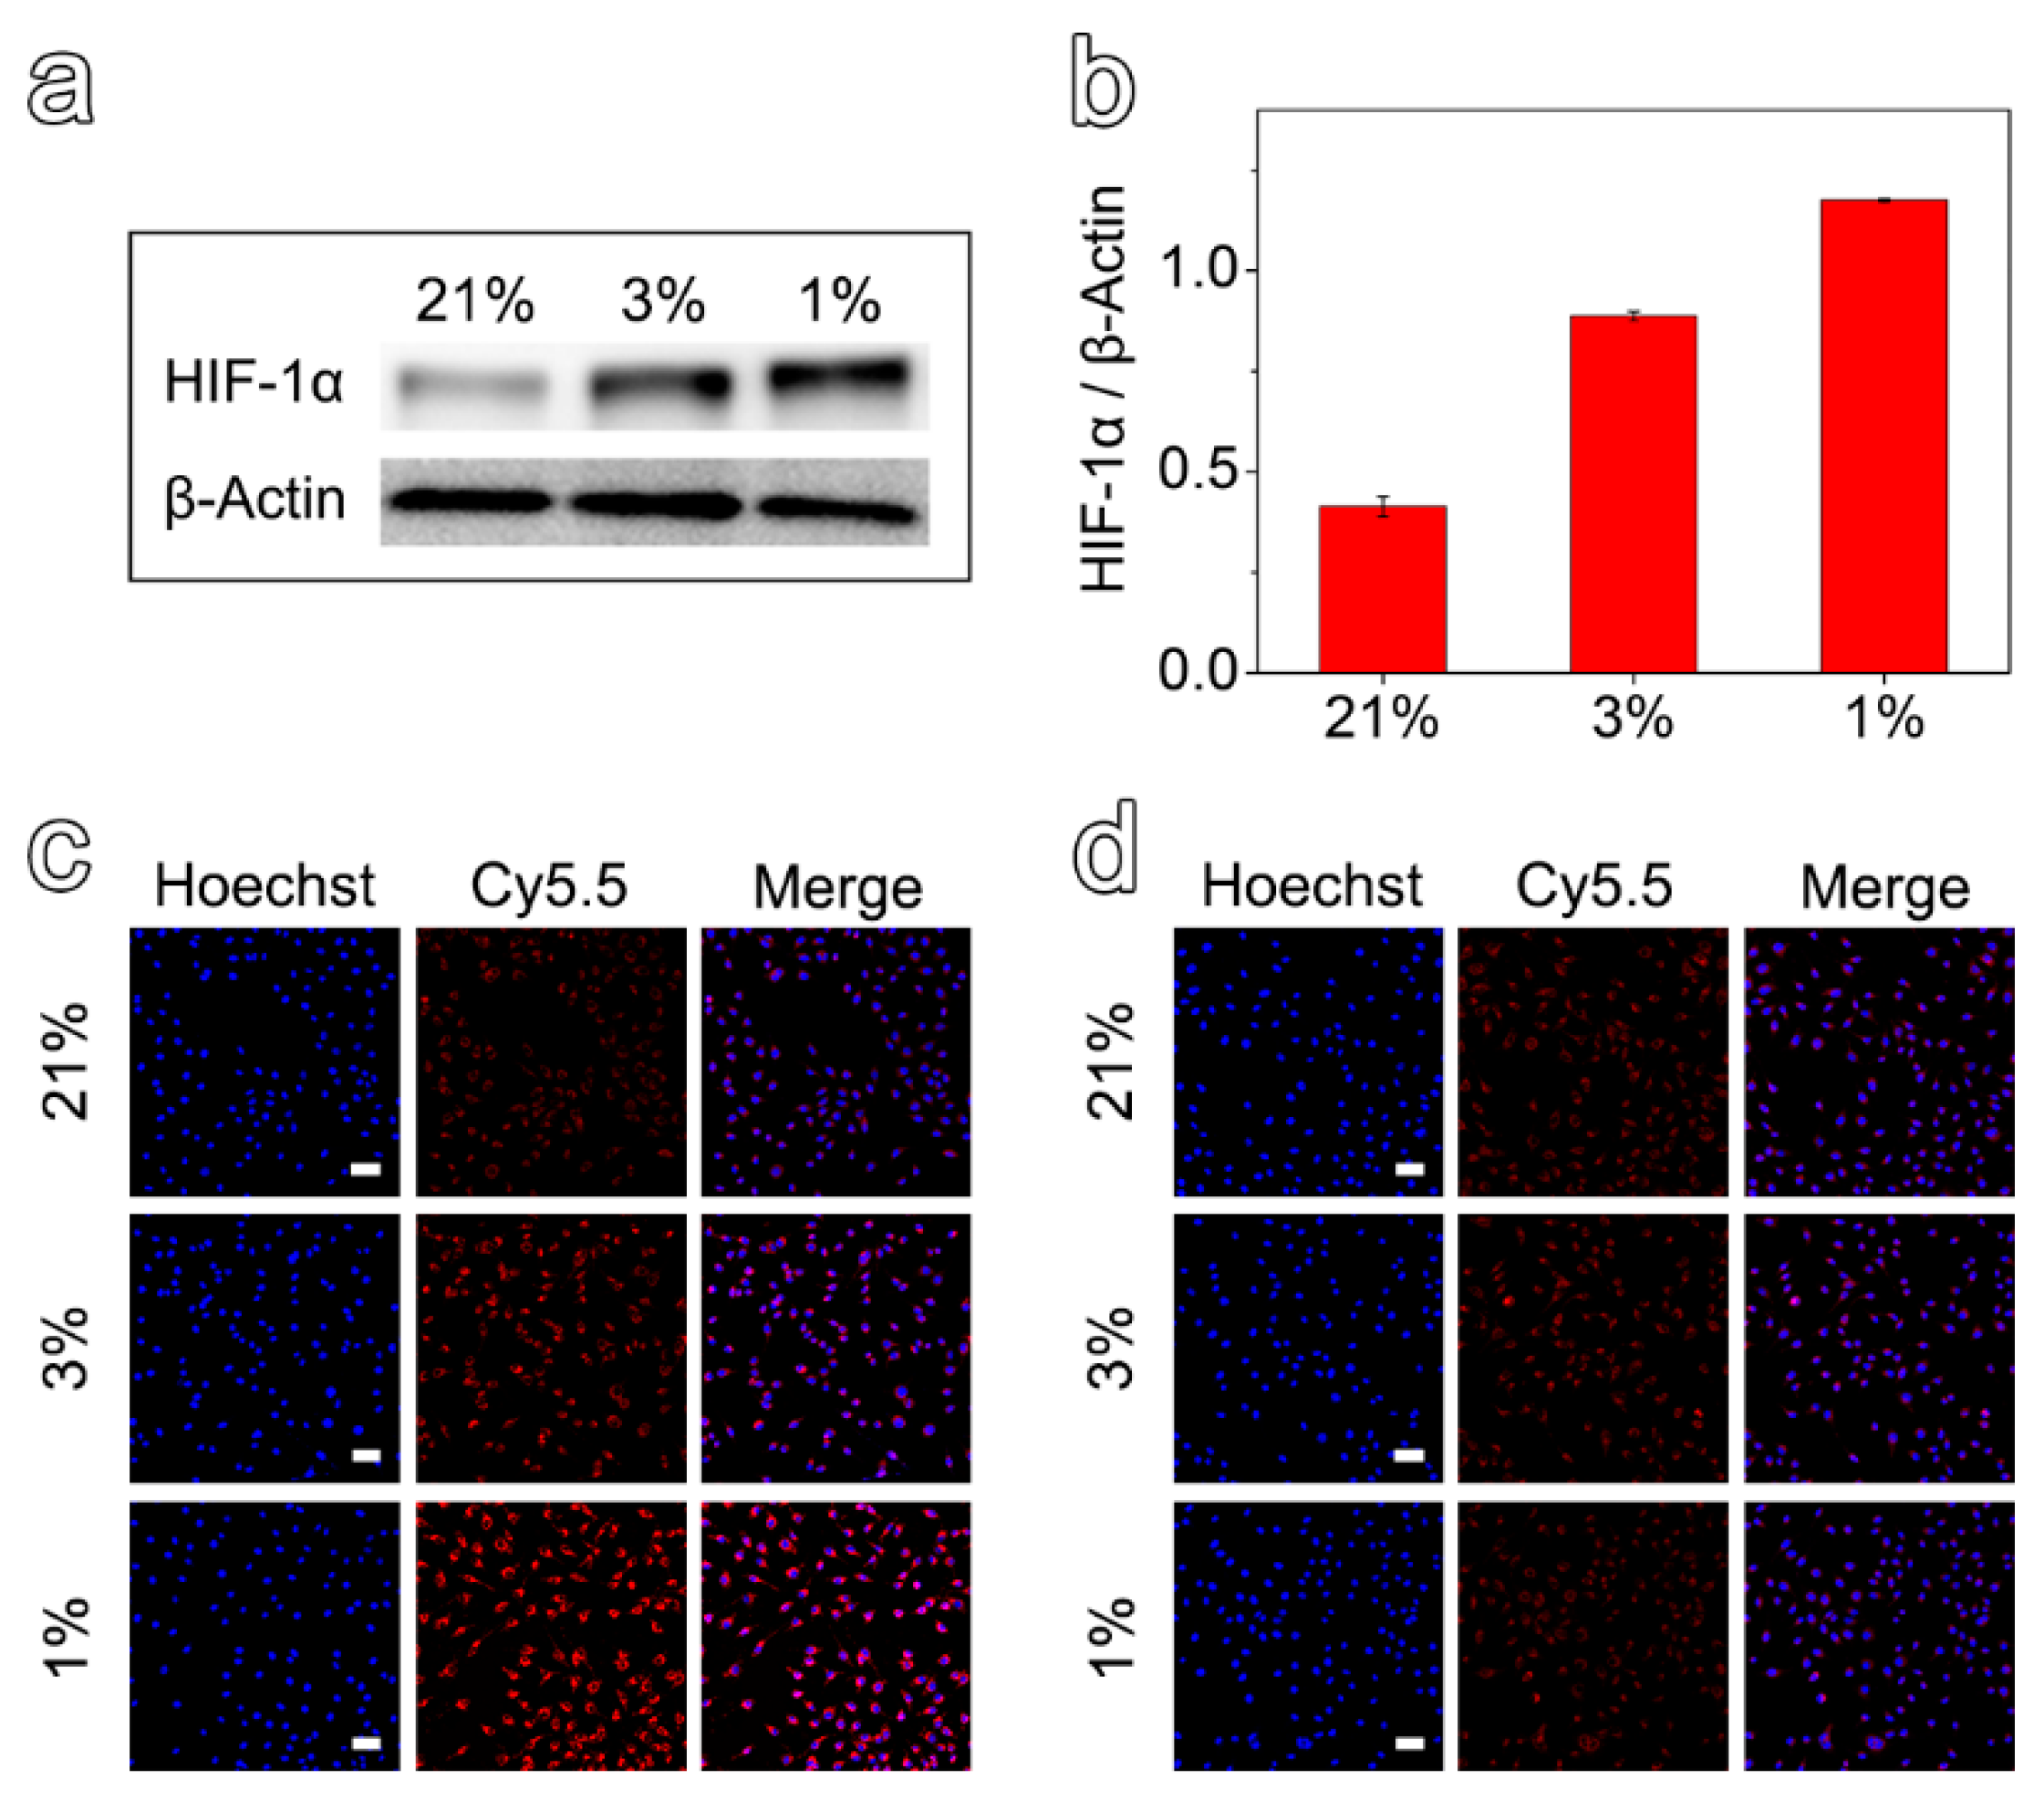

3.3. In Vitro Specificity and Cytotoxicity of Hypoxia-Sensitive MRI Nanoprobes